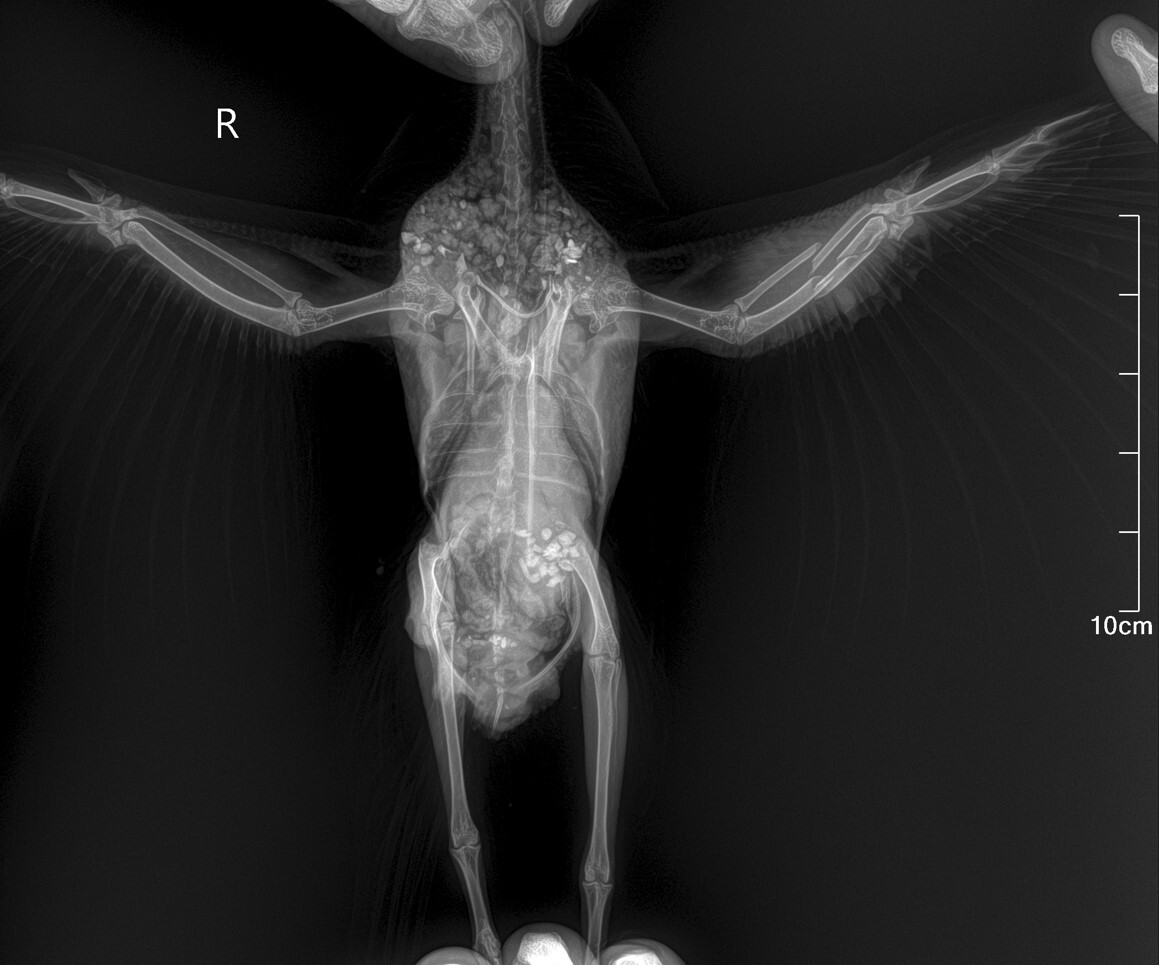

Голубь измучился и много очень выпил воды после "наложения" шины . На следующий день повёз к ветеринару, потому-что лапа начала чернеть (решил, что сепсис...). Ветеринар обрадовал, что это не сепсис, а зелёнка. Сказал что зелёнкой мазать нельзя голубю лапу - там каппиляры и тонкая кровеносняа система. И шину накладывать не надо было, сказал. Также сразу сказал, что сломано крыло. Сделали рентген. Предложил операцию за 10 тысяч, но результат 50/50. Денег не было, купил обезболивающее, антибиотик и оставил птицу на самореабилитации - без шины, без повязки на крыло. Только зелёную гречку давал, перловку. просо, пшеницу, камень минеральный для птицы, витамины, и немного обезболивающего и антибиотиков вначале.